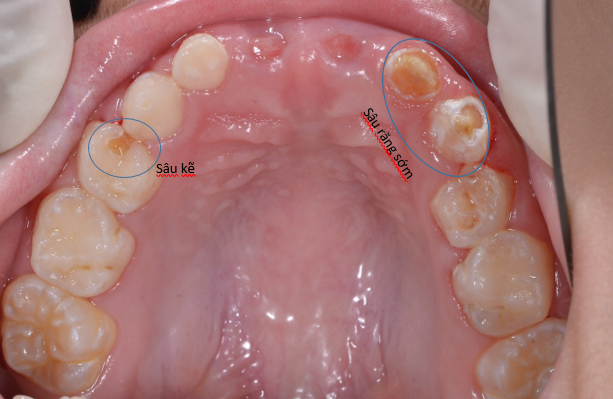

Đây là trường hợp bé 7 tuổi tới khám, bé bị sâu răng do bú bình từ nhỏ nhưng không được điều trị. Sau khi thăm khám bác sĩ đánh gía và đưa ra kế hoạch điều trị cụ thể như sau:

2. Sâu răng sớm hai hàm : mất men răng, mất mũi rãnh và hình dáng nên việc nhai thức ăn bị kém. Điều trị: trám và phục hồi với mão kim loại cho trẻ em.

3. Răng cối lớn vĩnh viễn mới mọc: có dấu hiệu mất khoáng- giai đoạn sớm của sâu răng. Cần trám phòng ngừa Sealant

5. Răng sâu kẽ làm cung răng bị mất khoảng, sau này răng vĩnh viễn mọc có thể bị chen chúc: chụp phim kiểm tra, giữ khoảng và tạo khoảng sau khi đánh giá mẫu hàm, phim.